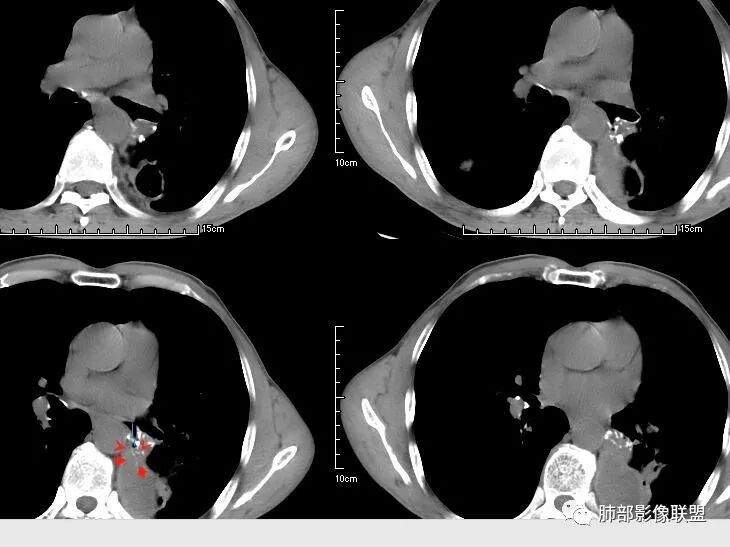

肺是发生转移瘤最多的脏器,几乎所有恶性肿瘤都可转移到肺,血行转移是最重要的转移途径。典型的肺转移瘤表现为多发圆形、大小不一的实性结节,边缘一般光整,多位于肺周边,多能明确诊断。空洞型肺转移瘤相对少见,约占肺转移瘤4%,其中70%为鳞癌转移;常见的空洞型肺转移瘤的原发恶性肿瘤多见于头颈部的鳞状上皮癌、胃肠道的腺癌和女性的生殖系统肿瘤以及其他部位的肉瘤等,组织学以鳞癌和腺癌最多见。

空洞型肺转移瘤成因尚不完全明确, 可能与鳞癌中心角化物排空 、腺癌黏液样退变后黏液排空 、肿瘤血供不足引起坏死 、肿瘤继发脓肿 、化疗等机制有关,其中部分薄壁囊腔样结可能是肿瘤细胞沿着原有的肺大泡或其它囊性结构生长或者肿瘤向小支气管侵犯引起活瓣性阻塞而形成 ,但无一种机制能解释全部现象。空洞或囊腔大小并不反映病情变化, 其临床意义不大, 而瘤灶的数目及大小, 特别是瘤灶实性成分的多少才可能更准确反映病情变化。肺癌形成空洞与其肿瘤本身性质有明显联系,肿瘤分化程度差,倍增时间越短,恶性程度越高,组织液化坏死形成空洞倾向越明显;鳞癌空洞偏大,内缘不规则,常易形成X线平片中癌梁样改变与CT中壁结节样改变;而腺癌空洞大小不定,洞内分隔明显,内缘不规则,且较难于形成壁结节等改变;合伴空洞的肿瘤边缘情况也对判断肿瘤性质有帮助。

国内文献将空洞的形态、壁的厚度及内壁情况将转移性空洞大致分为4大类:

(1)囊样空洞, 呈圆形或类圆形, 直径>15 mm,壁薄 (1 ~ 2 mm)而均匀 ,内壁欠光整 ;

(2)小环形空洞 ,呈圆形 ,壁薄 (2 ~ 4 mm)而均匀 ,直径≤15 mm, 内壁光整;

(3)泡样空洞, 呈圆形或类圆形 ,壁厚 ( >4 mm),内壁光整;

(4)不规则空洞, 洞腔形态不规则, 壁厚 ( >4 mm)且不均匀, 内壁不光整;

其中囊样空洞和小环形空洞属于薄壁空洞,泡样空洞和不规则空洞属于厚壁空洞,其中腺癌空洞型肺转移瘤主要表现为小环形空洞,以下3个病例均表现为小环形空洞的转移瘤:

本病例左肺下叶肿块,有深分叶、毛刺、胸膜牵拉凹陷、支气管截断及纵隔内淋巴结肿大等征象,都均支持病灶为恶性,如腺癌,而且叶间裂的多发结节也提示是腺癌来源可能大;双肺多发结节、肿块,大部分病灶有分叶、毛刺及胸膜凹陷的恶性征象,与原发肿瘤本身的性质有关,所以应该与左肺下叶肿块同源,而且双肺多发病灶内空洞也具有多样性;

此病例中空洞形态多样,内壁不光整,有分隔影,周围未见明显卫星灶及钙化灶,结核不太符合;患者病史慢性病史,无明显发热,缺乏中毒临床表现,急性感染基本排除;各种中性粒细胞胞浆抗体阴性,没有鼻窦炎,肾脏等病史,基本排除血管炎;霉菌性空洞常见于免疫机能低下者, 常为空洞、肺炎、伴“ 晕圈”征的结节及支气管扩张合并存在。